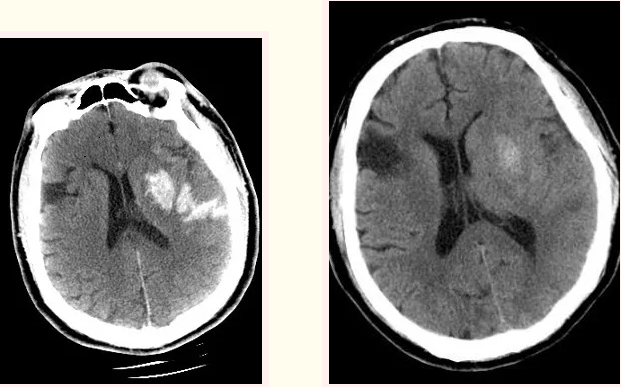

术后即刻复查头部CT造影剂外渗情况和术后24h复查头CT造影剂明显吸收